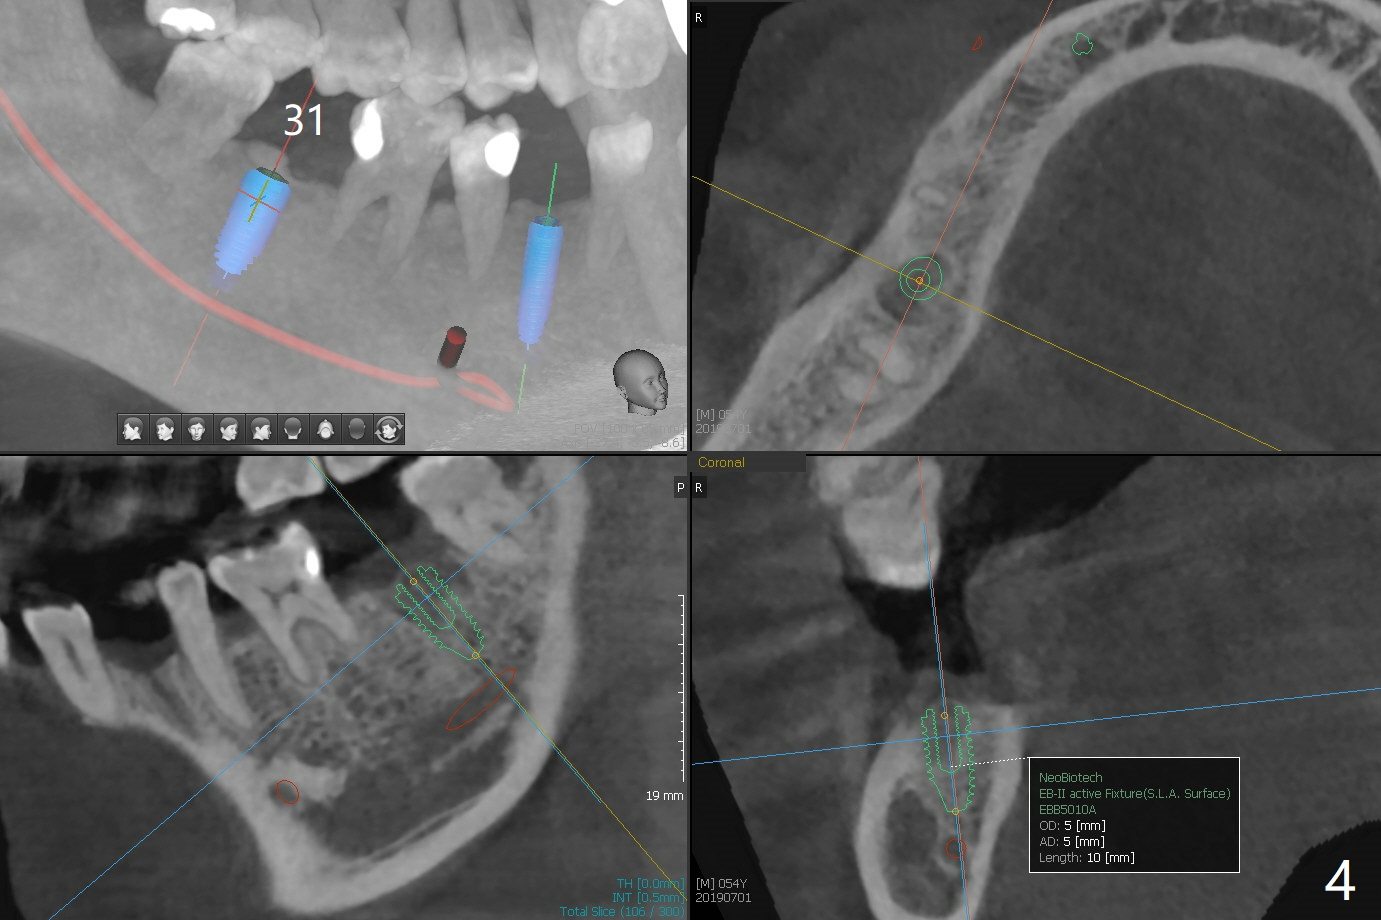

A 54-year-old man returns for #28 and 31 implants 3 months post extraction (#8,9 implants 4 years 5 months post cementation, Fig.1). The buccal plate at #28 is concave (Fig.2 *). After 2.2 mm drill to the depth as lingual as possible (Fig.3 L), use bone expanders through the guide to push the buccal plate out. Use Magic split or bone scalpels and blades to facilitate the expansion if needed. Place mixture of autogenous bone from #18 (Fig.4) and allograft buccally before implant insertion. Vertical fracture of the mesial root at #18 is an incidental finding (Fig.5 M). To avoid the impacted 3rd molar, osteotomy will be initiated as mesial as possible (Fig.6).